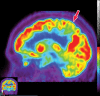

Neurodegenerative diseases are a devastating group of disorders that can be difficult to accurately diagnose. Although these disorders are difficult to manage owing to relatively limited treatment options, an early and correct diagnosis can help with managing symptoms and coping with the later stages of these disease processes. Both anatomic structural imaging and physiologic molecular imaging have evolved to a state in which these neurodegenerative processes can be identified relatively early with high accuracy. To determine the underlying disease, the radiologist should understand the different distributions and pathophysiologic processes involved. High-spatial-resolution MRI allows detection of subtle morphologic changes, as well as potential complications and alternate diagnoses, while molecular imaging allows visualization of altered function or abnormal increased or decreased concentration of disease-specific markers. These methodologies are complementary. Appropriate workup and interpretation of diagnostic studies require an integrated, multimodality, multidisciplinary approach. This article reviews the protocols and findings at MRI and nuclear medicine imaging, including with the use of flurodeoxyglucose, amyloid tracers, and dopaminergic transporter imaging (ioflupane). The pathophysiology of some of the major neurodegenerative processes and their clinical presentations are also reviewed; this information is critical to understand how these imaging modalities work, and it aids in the integration of clinical data to help synthesize a final diagnosis. Radiologists and nuclear medicine physicians aiming to include the evaluation of neurodegenerative diseases in their practice should be aware of and familiar with the multiple imaging modalities available and how using these modalities is essential in the multidisciplinary management of patients with neurodegenerative diseases.©RSNA, 2020.